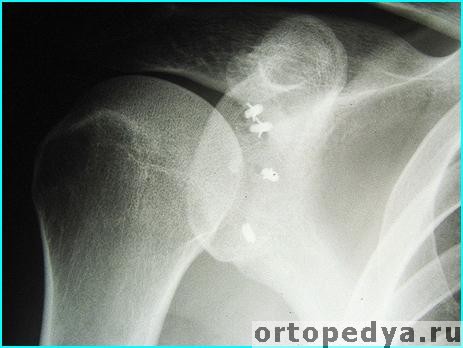

На послеоперационной рентгенограмме с титанами фиксаторами:

При использовании рассасывающихся якорей на снимке они не видны.